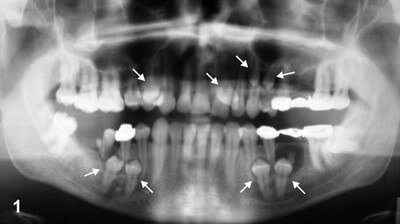

Picture 5: Multiple Supernumerary Teeth on Orthopantomograph

Image Source: intelligentdental.com